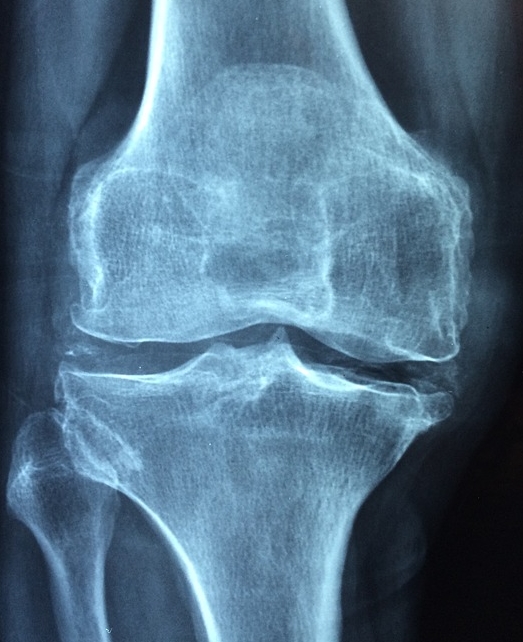

- X-ray, MRI, 초음파 검사: 관절 손상 여부를 확인하기 위해 촬영하는 검사입니다.